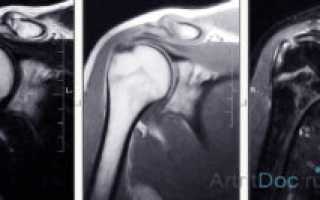

Результатом МР-сканирования являются послойные изображения исследуемой области в трех, взаимноперпендикулярных проекциях. Анализом фото занимается врач-рентгенолог, который фиксирует и описывает любые отклонения структуры сустава от нормы.

На снимках преобладают серые оттенки, интенсивность которых зависит от плотности обследуемых структур. При необходимости на экране монитора создается трехмерное изображение, наиболее информативное при проведении МРТ с контрастным веществом.

Интерпретацией полученных результатов занимается врач лучевой диагностики. Расшифровка обычно не занимает больше 2 часов, однако при загруженности рентгенолога пациентам приходится ждать результатов в течение суток. Что показывает МРТ плечевого сустава:

Во время расшифровки результатов оценивается состояние костных поверхностей, выстланных хрящевыми тканями. В норме на них не должно быть выраженных дефектов. Исследуются и расположенные рядом с сочленением связки, сухожилия, нервные пучки, мышечные волокна. Изменения мягкотканных структур часто указывают на вялотекущий воспалительный процесс.